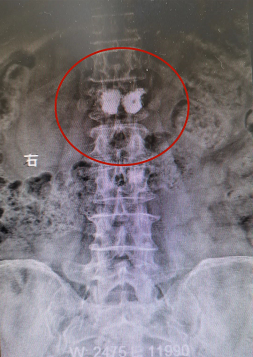

患者骨水泥椎体成形术术后影像

患者孙某某,女,83岁,早上晨练后摔伤出现腰背部疼痛,起立行走困难,在家卧床休息7小时后疼痛未缓解,来院门诊行腰椎X光片检查后提示:腰L1椎体压缩性骨折,告知患者及其家属诊疗方案后,患者及其家属要求手术治疗。入院第二天予患者行腰L1骨水泥椎体成形术,术后当天患者自觉胸腰背部疼痛明显缓解,术后第二天患者下床自行活动良好。